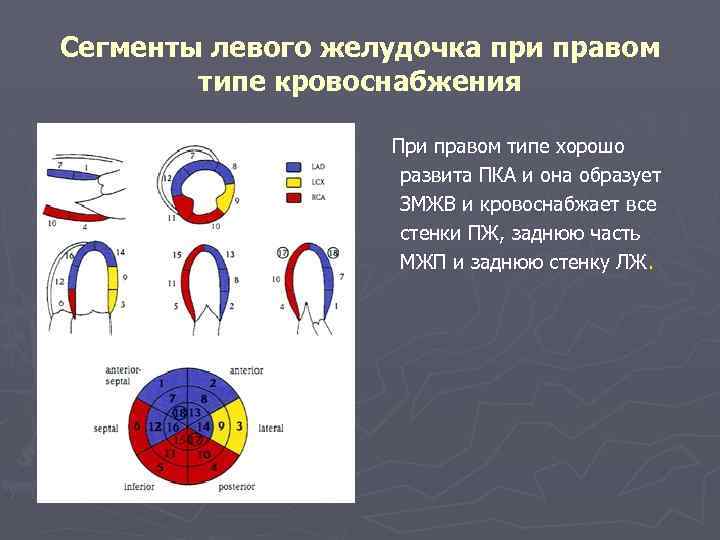

Сегменты левого желудочка при правом типе кровоснабжения При правом типе хорошо развита ПКА и она образует ЗМЖВ и кровоснабжает все стенки ПЖ, заднюю часть МЖП и заднюю стенку ЛЖ.